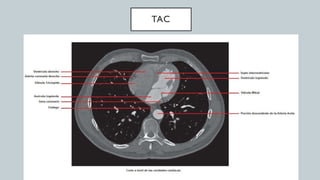

El documento detalla la anatomía del corazón y su ubicación en la caja torácica, incluyendo estructuras como las aurículas, ventrículos y arterias. También se abordan técnicas de diagnóstico por imagen, como radiografías y TAC, para visualizar la morfología cardíaca. La información está dirigida a estudiantes de medicina y profesionales interesados en la anatomía cardíaca.